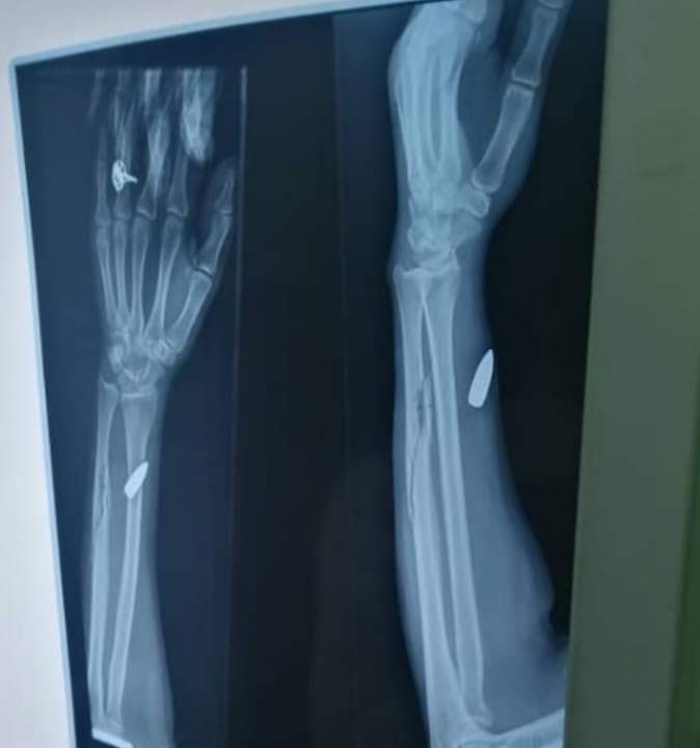

أصابت رصاصة راجعة امرأة في محافظة إب، اليوم الاثنين، عقب إطلاق نار كثيف بحفل زواج.

وقالت مصادر محلية لـ "المشهد العربي"، إن الرصاصة اخترقت سقف مطبخ الضحية – المصنوع من مادة الزنك - واستقرت في ذراعها.

ولفتت إلى نقل المصابة إلى المستشفى للسيطرة على النزيف وتلقي الإسعافات العاجلة.